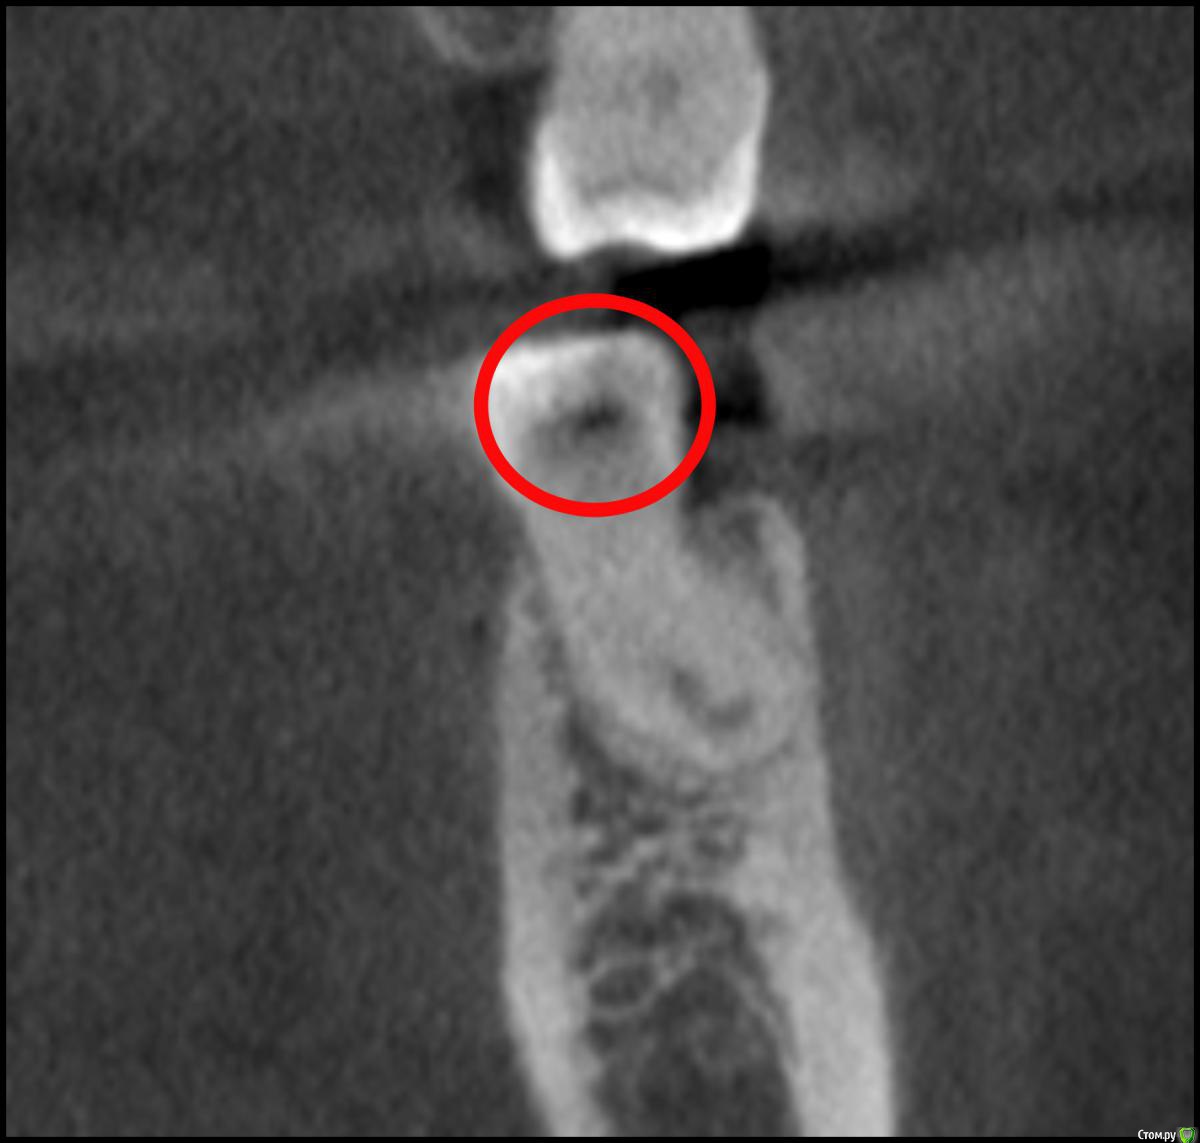

Nick-ev Опубликовано 6 апреля, 2019 Поделиться Опубликовано 6 апреля, 2019 2 месяца назад запломбировали зуб, не болел вообще, но стоматолог увидел что то на нем.Недавно делал КТ и увидел затенение под пломбой.Пожалуйста посмотрите, что это на снимке. Ссылка на комментарий

Nick-ev Опубликовано 8 апреля, 2019 Автор Поделиться Опубликовано 8 апреля, 2019 По кт кариес под пломбой диагностировать практически невозможно, его обычно делают в других целях а что это за темное пятно под пломбой? Ссылка на комментарий

___49___ Опубликовано 8 апреля, 2019 Поделиться Опубликовано 8 апреля, 2019 а что это за темное пятно под пломбой?Возможно кариес, возможно рентген не контрастный цемент или др материал .. Такого рода клинические случаи получают диагноз по совокупности данных объективных исследований, жалоб и клинических проявлений - что можно сделать только в кресле у врача. Коллега права - под пломбой диагноз по КТ весьма затруднителен, а вот зуб сверху над тем что вы указали с кариесом и диагноз тут очевиден , так как пломбы нет и рентген не контрастное вещество в него до нас не закладывали . Ссылка на комментарий